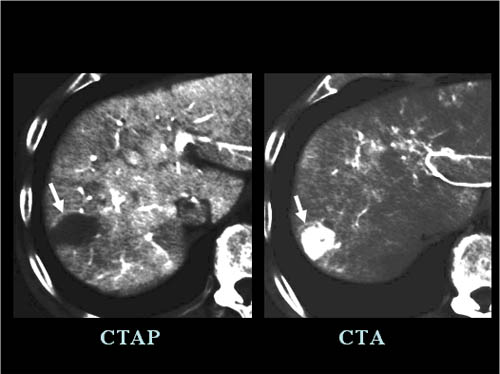

3.IVR-CTを用いたCTA(肝動脈造影時CT)/CTAP(門脈造時CT)

CTA/CTAPとは、肝臓に流れる血管(肝動脈や門脈)に造影剤を注入すると同時にCT検査を行う方法で、肝癌に対する検出能の最も高い検査のひとつです。進行肝癌ではCTAにてよく造影され、CTAPにおいては造影されず抜けて見えます。 早期の段階の肝細胞癌ではCTAでは造影されません。

【進行型肝癌のCTA/CTAP画像】